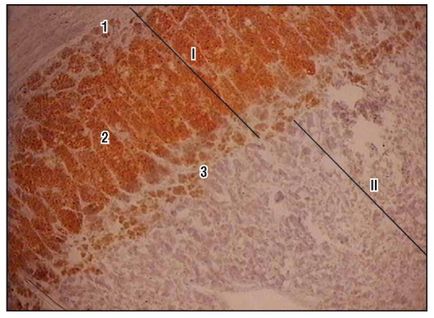

Fig. 173. Nadbochechnik (pictura pe nava III):

1 - substanță corticală: 1 - zonă glomerulară;